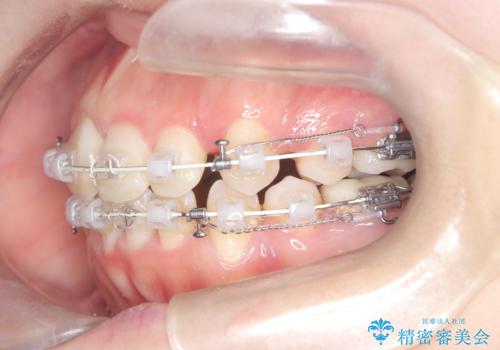

今回の矯正治療では、歯が並ぶスペースを確保するため、上下左右の小臼歯を抜歯しました。装置には目立ちにくい審美ワイヤーを使用し、見た目に配慮しながら治療を進めました。抜歯によってできたスペースを利用して歯を並べ、前歯のデコボコを解消。同時に、歯列全体を動かすことで、上下の歯がきちんと閉じる開口も改善しました。治療期間は約2年間。治療の結果、コンプレックスだった前歯のデコボコと開口が解消され、整った美しい歯並びと、しっかり咬める機能的な咬み合わせを獲得していただけました。